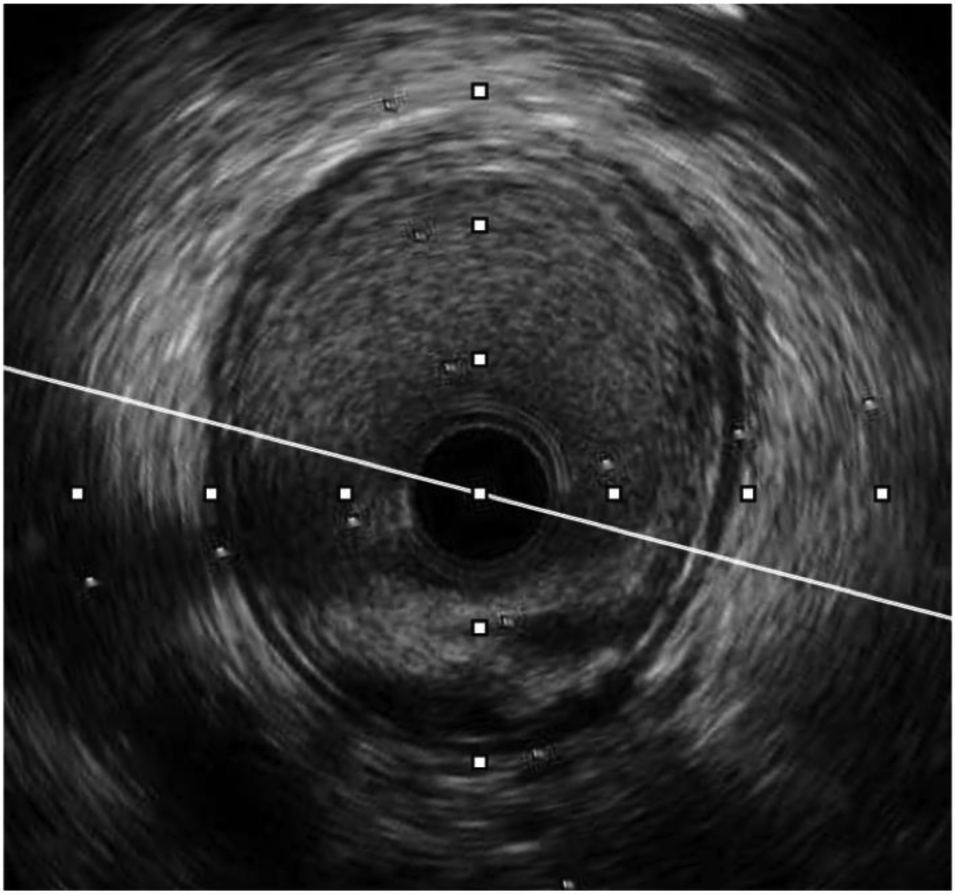

In our study, 98.3% of patients received intravascular ultrasound prior to implantation to evaluate the lesion characteristics and to select the appropriate scaffold size, as well as an intravascular ultrasound after the intervention to evaluate the effectiveness and success rate of the procedure. All of the patients received post-intervention balloon dilation. The efforts to follow the same process have helped the procedure to achieve a successful intervention rate of 100% (Table 6). Figures 3–5 displayed IVUS imaging of a patient who underwent Magmaris implantation using IVUS.

Figure 4

Pre-procedure IVUS of the same patient (from Figure 3) showed fibrotic lesion with plaque rupture.